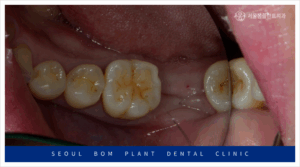

오늘 소개할 환자분은 50대 여성으로,

아래턱 오른쪽 어금니가 가만히 있어도 아프고,

볼이 많이 부어 있는 증상으로 저희 치과를 내원하셨습니다.

이 환자분은 저희 치과에 오기 전에

다른 치과에서 진료를 받았으나,

심한 골 소실로 인해 임플란트 치료가

불가하다는 판단을 받으셨다고 합니다.